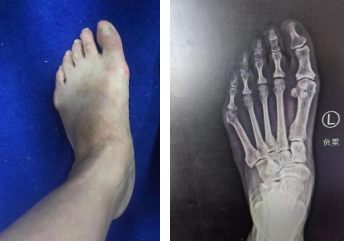

接诊的业务院长石荣剑通过查体及X光片检查,发现吴女士的脚不仅有拇外翻,还有小趾内翻,整个前脚掌相比较正常尺寸宽大了一半,小趾外侧胼胝已经很厚了,需要尽快治疗。

术前设计(左图) 术后即刻(右图)